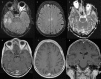

IgLON5-associated encephalitis is a syndrome with different clinical presentations consisting of sleep dysfunction, bulbar dysfunction, chorea, and progressive supranuclear palsy-like symptoms whereas dysautonomy and cognitive decline usually appear in later stages of the disease. We report a case of a patient with IgLON5-associated encephalitis presenting with rapidly progressive cognitive decline and atypical inflammatory lesions on brain magnetic resonance imaging, oligoclonal bands on cerebrospinal fluid, anti-IgLON5 antibodies exclusively of the IgG1 class, and a fierce inflammatory reaction on brain biopsy, who responded favorably to immunotherapy.